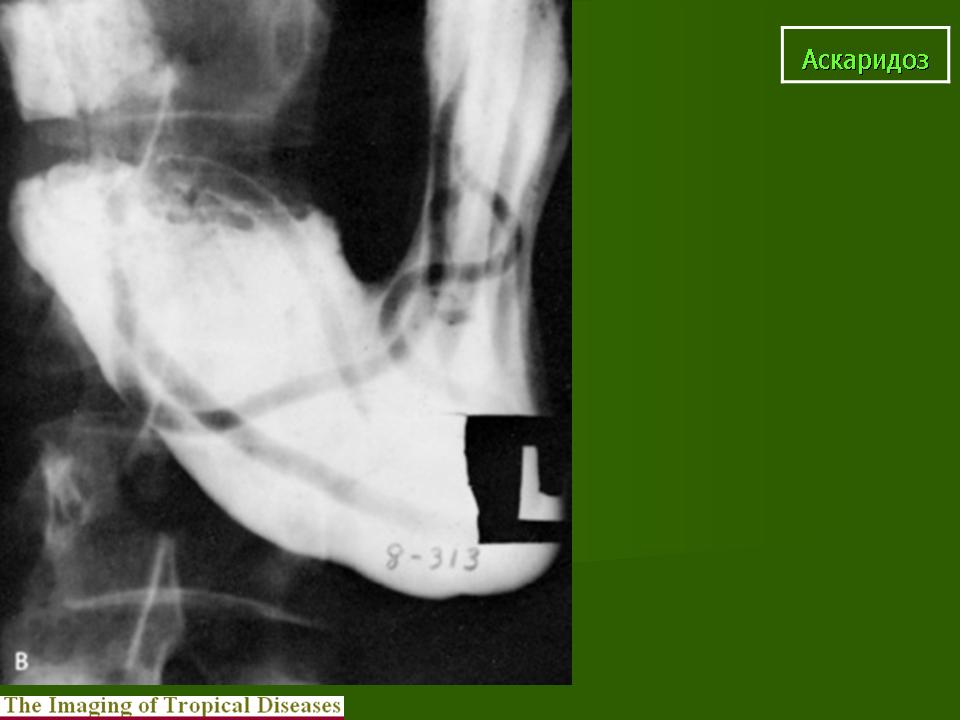

Пар. Аскаридоз. +

Аскаридоз.